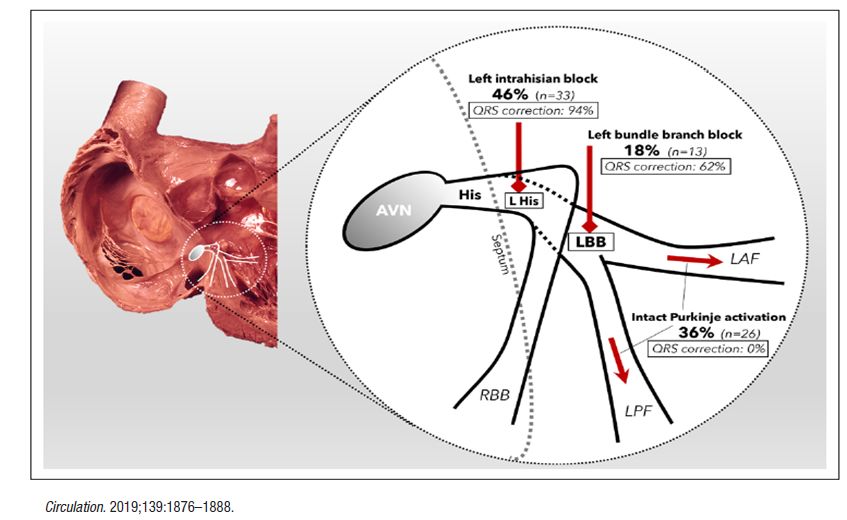

希氏束起搏纠正束支传导阻滞

经间隔内左束支区域起搏

左束支位于希氏束远端的左室间隔面内膜下

相比希氏束起搏,左束支区域起搏能获得更低更稳定的起搏阈值和更高的感知参数

希浦系统起搏能解决所有问题吗?

希氏束起搏可以作为左束支阻滞的心肌病患者双室起搏的替代选择。

在合并心衰的完全性左束支阻滞及室内传导阻滞患者中,希氏束起搏不能完全纠正传导异常。